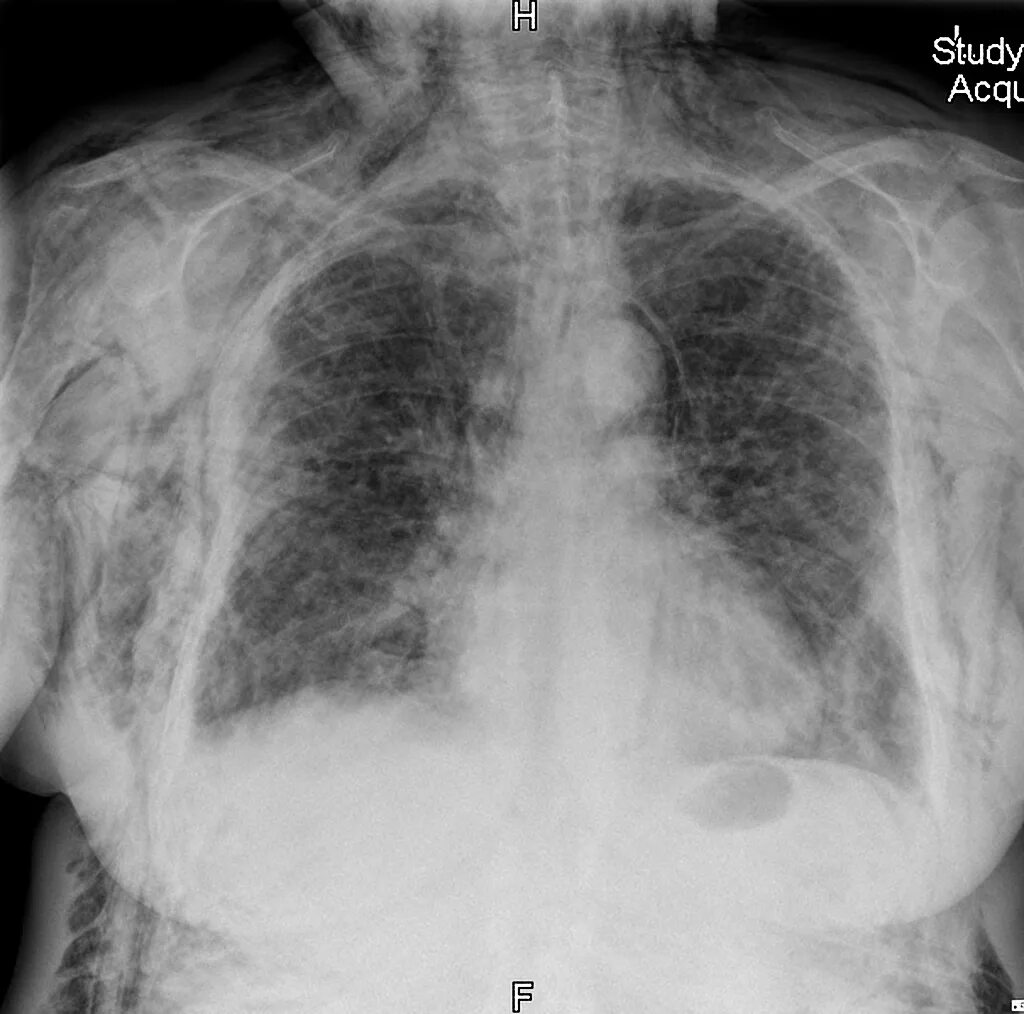

Эмфизема мягких